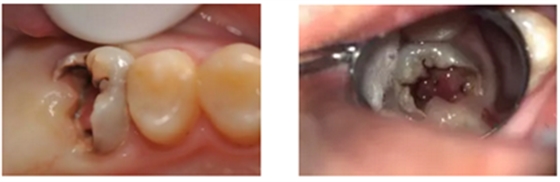

1、局麻下,Er-YAG激光切除增生牙龈

2、使用组织排开橡皮障夹(#B-1)上橡皮障,障布边缘翻转,隔离牙龈,封闭患牙。

3、去净腐质后,剩余健康牙体组织位于龈下,考虑行龈壁提升,因需使用成型片,拆除橡皮障。

4、使用成型片隔离牙龈,保证边缘密合不渗漏,SDR树脂龈壁提升。

5、进行正式根管治疗前,仍需对近中邻面龋坏牙体组织进行处理。

6、上橡皮障,去除近中龋坏组织,SDR树脂制作近中邻面假壁。

7、初步恢复牙体完整性后上橡皮障,开髓,3% NaClO冲洗,揭除髓顶,修整开髓洞形,去除髓腔牙髓组织。